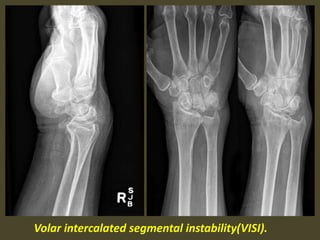

A simple approach is to consider the lunate

which is usually the easiest carpal bone to

visualize on a lateral wrist image. If the

lunate is abnormally tilted in a dorsal

direction on a standard lateral wrist image,

a DISI should be considered. If the lunate is

abnormally tilted in a volar direction a VISI

should be considered. DISI is due to

disruption of the scapho-lunate articulation.

VISI is secondary to disruption of the luno-

triquetral articulation.

Volar intercalated segmental instability(VISI).

VISI with volar tilting of the lunate.

VISI with luno-triquetrum ligament tear and volar tilting of the lunate.

VISI deformity secondary to Lunotriquetral ligament tear.